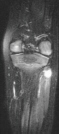

MRI examination of the left knee displayed a 2 cm. by 0.8 cm. lobulated

mass in the region of the common peroneal nerve with no enhancement (images

3and 4). On the T-2 weighted sequences there was abnormal increased signal

of the tibialis anterior, extensor digitorum longus and peroneus longus

muscle bellies suggesting atrophy (images 5, 6 and 7).